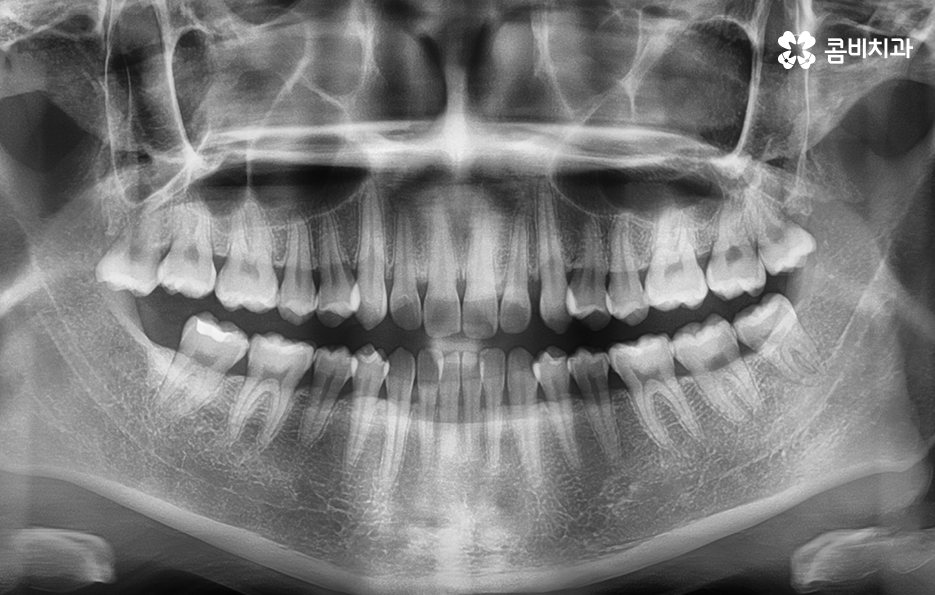

교정에 대해 알아보시면 단순히 치열을 가지런하게 재배열 혹은 펴는 개념만이 아니라 치아교정을 통해 부정교합을 치료하여 치아의 기능적인 부분을 개선하거나 얼굴 변화에 대한 부분, 치아의 건강 등 종합적으로 알아봐야 할 점들이 많다는 것을 알 수 있는데요.

이 중에서는 발치 여부에 대해서도 많은 고민이 되는 부분 중에 하나일 거예요. 교정 치료에서 발치를 하는 경우에는 보통 작은 어금니를 발치하여 치아의 이동 공간을 확보하는 경우가 많은데 아무래도 생니를 발치한다는 생각에 발치는 무조건 안좋다고 느끼거나 거부감을 느끼시는 분들도 많이 있어요.

교정 치료는 크게 발치와 비발치치아교정으로 나뉠 수 있는데 비발치치아교정의 경우에는 아무래도 치아가 움직이는 양도 적고 그에 따라 교정 기간도 짧은 편에 해당되고 있어요.

그렇기 때문에 비발치치아교정이 좋다고 생각하기 보다는 개인에 따라서는 치아의 이동 공간 확보를 충분히 하기 위해 발치가 필요한 경우도 있고 얼굴 변화나 부정교합의 개선을 위해 발치가 필수적인 경우도 있을 거예요

단순히 비발치치아교정이 발치를 안해도 되니 무조건 좋다고 판단하기 보다는 각 개인의 치료 목적과 구강 및 골격, 얼굴형의 상태를 종합적으로 정밀 검진하여 자신에게 적합한 치료 계획을 잘 세우는 것이 중요하다고 강조드리고 있어요